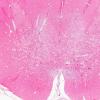

Leigh's Dz (4)